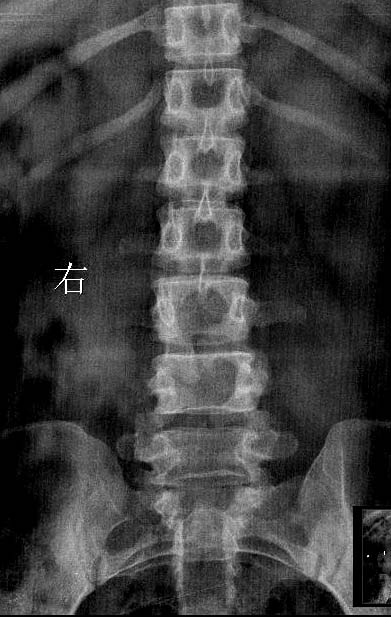

女.29岁.先天髋关节脱位.腰椎后部向外膨出.外院诊断骨肉瘤.我院诊断夏科氏关节病。

该患者有脊柱裂和右侧髋臼发育不良,踝关节改变符合神经性骨关节病,必要时结合临床排除结核.

支持:1、脊柱裂;

2、右侧髋臼发育不良伴半脱位;

3、双踝关节夏科氏关节病。

支持:1、隐性脊柱裂;

3、双踝关节改变符合神经营养性关节病(夏科关节);

4、双侧髂骨致密性骨炎。

1、脊柱裂;伴脊髓脊膜膨出?建议mri检查,